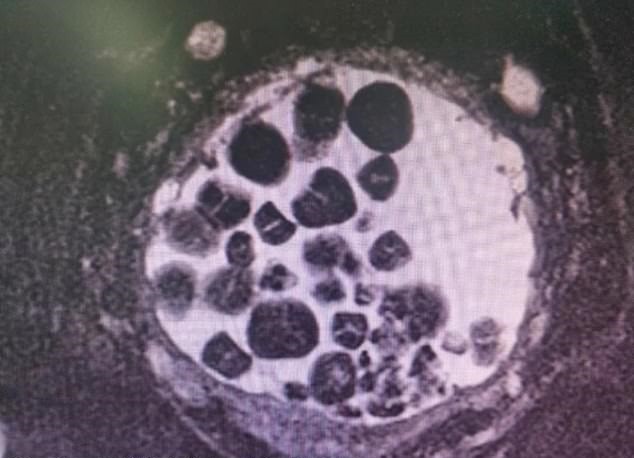

Ele foi então levado para fazer o raio-x e o que os médicos encontraram foi assustador. A bexiga de Liu estava tomada por diversos cálculos vesicais, como nunca tinham visto antes. Consequentemente, ele foi encaminhado com urgência para ser operado, com a retirada das pedras o quanto antes.

Na sala de cirurgia, a bexiga foi drenada para que pudesse se fazer o procedimento. Os médicos abriram a região e começaram a fazer a limpeza, retirando as pedras que lá estavam. Ao final, depois de retirar boa parte dos cálculos, eles já contabilizavam 100 pedras dos mais diversos tamanhos.